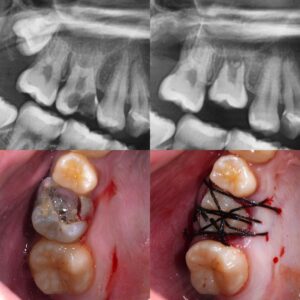

移植直後(〜1ヶ月)の痛みは「正常」であることが多い

移植手術は、歯を一度抜き、骨を削って新しい場所に植えるという、体にとって非常に大きなイベントです。

歯周組織の「火傷」と「打ち身」

歯を植えた直後の周囲組織は、いわば激しい打ち身や火傷を負ったような状態です。

移植した歯と周囲の骨がまだ完全に結合しておらず、噛む力(咬合圧)を支える準備ができていません。

この時期は「安静」が第一です。周囲の歯と固定(シンス)されているはずですので、極力その歯で噛まないようにしてください。